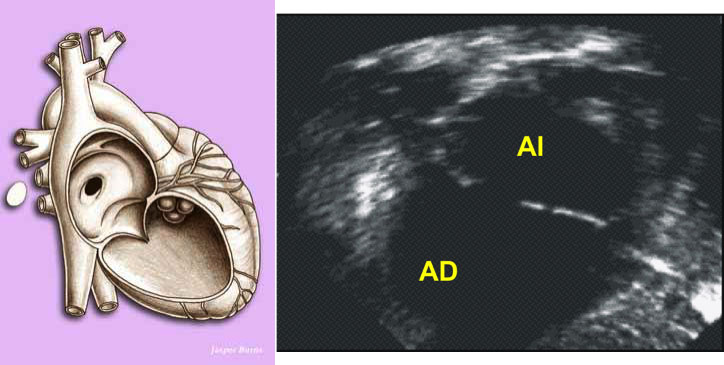

Coronary lesions appear between 1 and 4 weeks after the onset of fever in about 20% of untreated patients and are responsible for most of the mortality and morbidity of KD. Coronary dilatations of variable size can be detected, which mainly affect the proximal portion of the main coronary arteries. They can coexist with areas of stenosis and are susceptible to aortic thrombosis, causing myocardial infarction.

Due to its high availability, sensitivity and specificity, the echocardiogram is the technique of choice to detect coronary alterations. It must be done during diagnosis, at 2-4 weeks and periodically thereafter as a follow-up for patients with aneurysms. Other imaging techniques, such as magnetic resonance imaging (MRI) or multi-slice computed tomography (MSCT), may be useful for detecting distal aneurysms or determining the locations of complications such as thrombosis or occlusion. Conventional coronary angiography provides better defined image of the lesions, but should not be performed until inflammatory process is completely resolved.